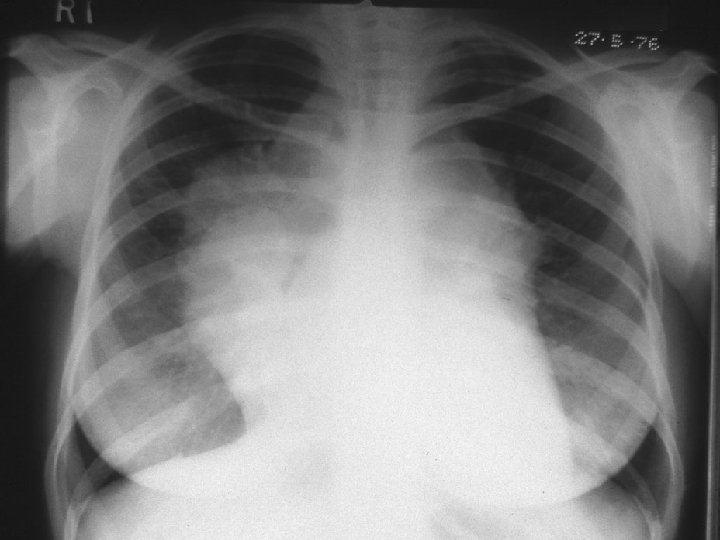

pulmonary Lymphoma.

Mediastinal Lymphoma

pulmonary Lymphoma.

Mediastinal Lymphoma